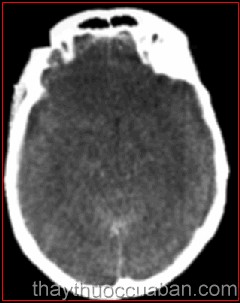

Phù não là sự tăng thể tích não do sự tăng tích tụ nước. Người ta chia phù não làm 3 loại chính:

Loại 1: Phù vận mạch : do tăng tính thấm mao mạch. Là thể phù thường gặp nhất, thường trong u não, tổn thương do viêm nhiễm (áp xe, viêm não), nhồi máu, xuất huyết não và dập não. Đặc trưng của loại phù vận mạch là: phá vỡ hàng rào máu não cục bộ gây thoát mạch và huyết tương giàu protein tích tụ và thấm khoang ngoài mạch máu phù.

Loại 2: Phù độc tế bào: do rối loạn chuyển hóa trong tế bào, rối loạn hoạt động kênh natri phụ thuộc ATP. Phù độc tế bào là sự sưng phồng cấp tính của tất cả các thành phần tế bào ( tế bào nội mạc, tế bào sao, neuron ) đi đôi sự giảm sụt thể tích của khoang ngoại bào não. - Thường thấy trong thiếu máu nuôi cấp tính ở não do bệnh lí tim mạch hoặc chấn thương sọ não.

Loại 3: Phù thủy tĩnh hay phù khoảng kẻ: do Gradien áp lực xuyên màng nội tủy, đẩy DNT từ não thất ra khoang ngoại bào.